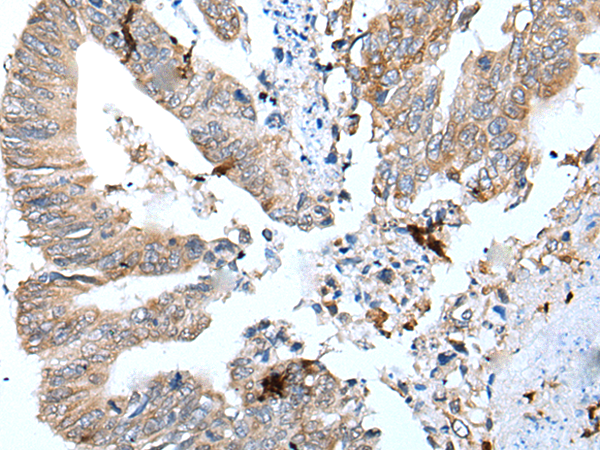

IHC positive control: |

Human colorectal cancer |

IHC Recommend dilution: |

25-100 |